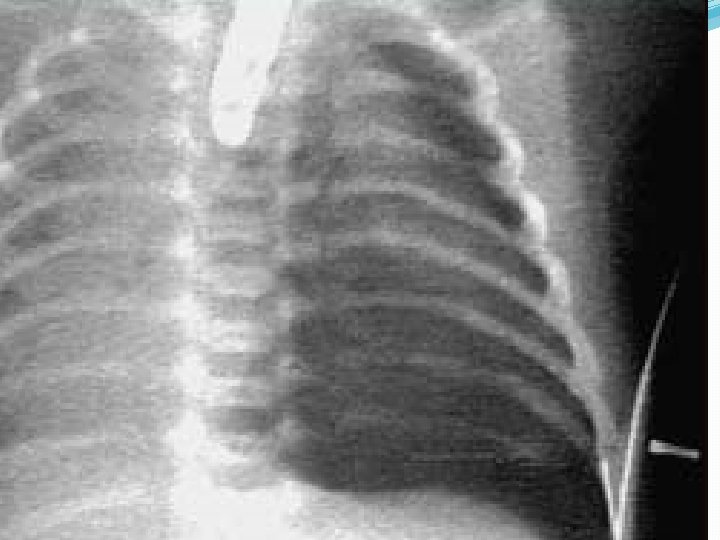

Hemotórax Masivo. �Es el resultado de la acumulación de sangre en la cavidad pleural. �La principal causa generalmente es por heridas penetrantes, menos frecuente es por desgarro de estos vasos en un trauma cerrado. �Clínicamente encontrará un paciente en shock, con colapso de los vasos del cuello por hipovolemia o con ingurgitación de estos por efecto mecánico de la cavidad pleural, hipóxico, ausencia de expansión en el hemitórax dañado y matidez a la percusión.

Cuadro clínico �Inspección ( Disnea ) �Palpación (disminucion del frémito ) �Percusión (Matidez , o hipo timpanismo) �Auscultación (Disminución murmullo vesicular)

Drenaje pleural � Todos ameritan como tratamiento un drenaje pleural con sonda de pleurostomia 0 toracostomía mínima.

¿Cuándo drenar un hemotórax? �Volumen: > de 500 ml �Sintomatología �Necesidad de presión positiva �Asociación con neumotórax